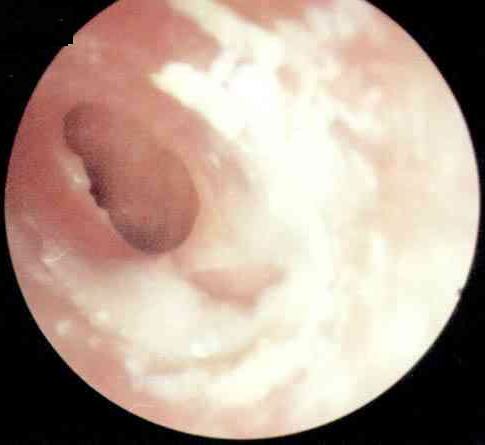

中耳炎病理图

中耳炎是引起鼓室硬化常见的病因。表现为鼓膜增厚,内陷。鼓室或乳突窦及乳突气房内充填软组织密度影,乳突气房含气减少或消失,鼓室及乳突内可以出现积液征象,听小骨破坏甚至消失,少部分患者可有乳突及鼓室壁的骨质破坏。但不会出现钙化。